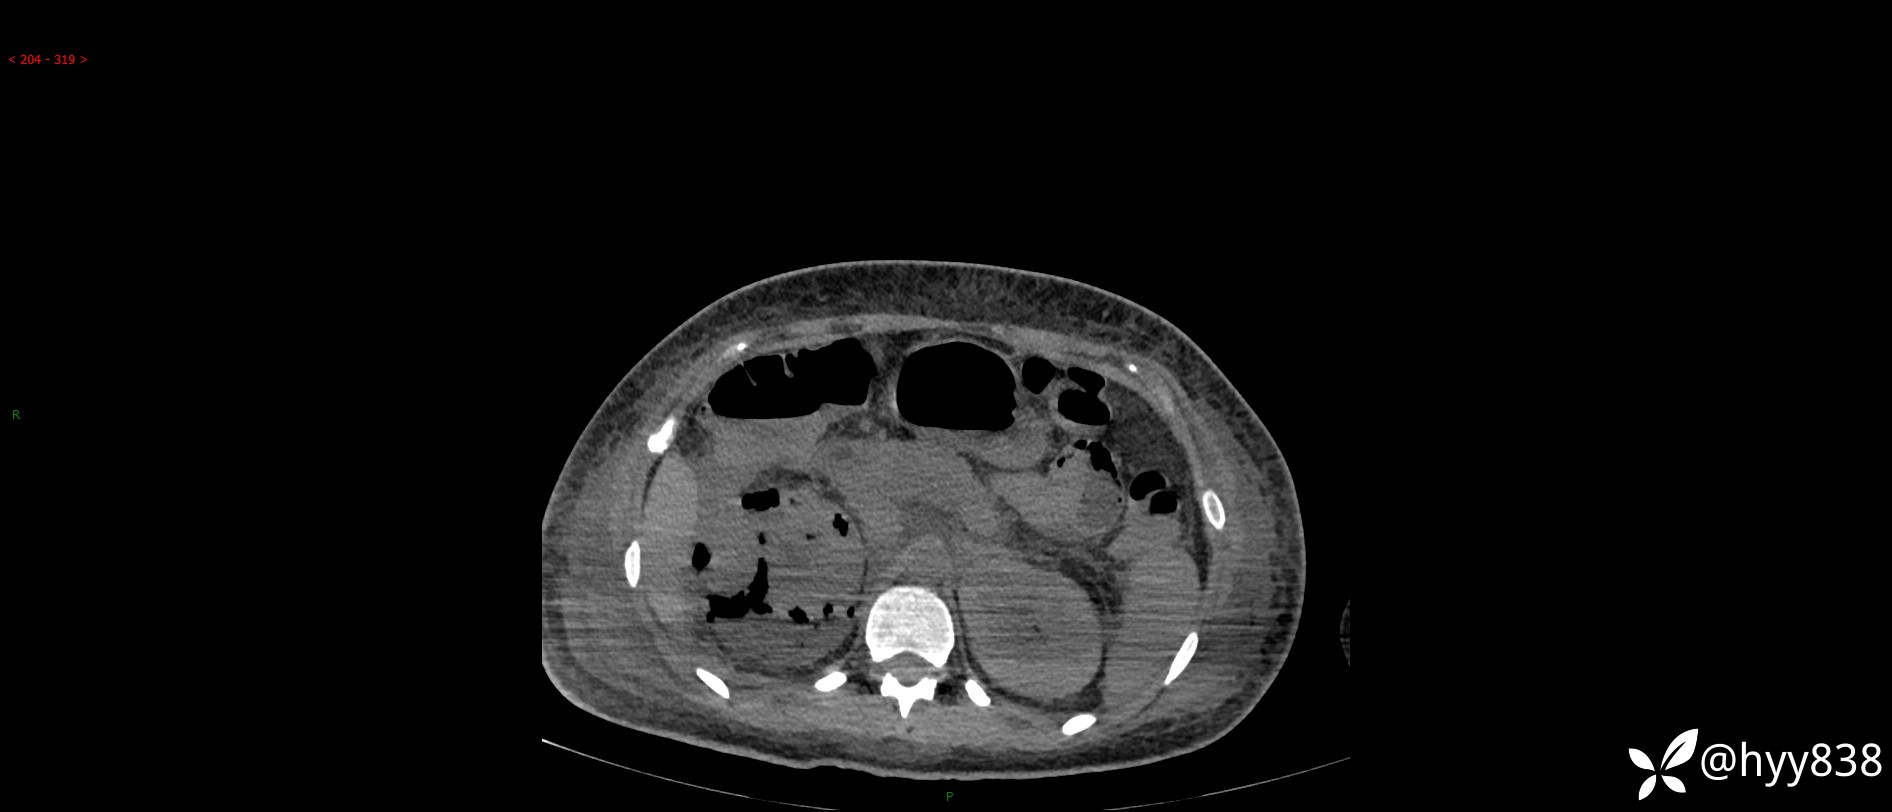

大年三十︱年轻女性,饮酒后突发腰痛,很意外---结果公布~

患者年龄:29岁

主诉:右侧腰部疼痛2天

简要病史:患者2天前和朋友聚餐饮酒时出现右侧腰部疼痛不适,呈间断性胀痛,伴发热、呕吐,无头晕、心慌、胸闷等不适,不伴有尿频、尿急、尿痛等症,院外与当地诊所输液对症治疗症状未见明显改善,今来我院急诊就诊全腹部CT自阅片考虑右肾周围炎,现患者为寻求进一步就诊,来我科就诊,我科以“右肾周围炎”收治入院。 起病以来,患者精神、饮食、睡眠可,大小便正常,体力体重无明显减轻。

临床诊断:肾周围炎

肾脏CT平扫